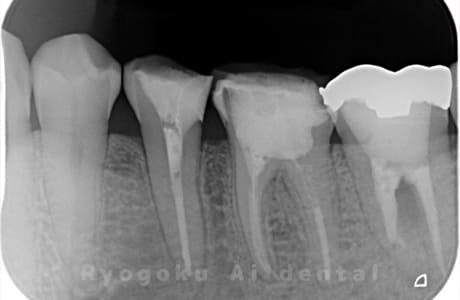

Case03

-

- 原因

- 重度カリエス、慢性根尖性歯周炎

- 治療内容

- 自家歯牙移植

- 治療費用

- 220,000円

他院で右下の根の治療を行い、セラミックを被せる説明をされていたが、根の治療が終わらないため転院された患者さんです。隣の親知らずの抜歯の必要性と、根の治療を行なっている歯牙の予後が悪いため、移植治療を提案し、右下の親知らずの抜歯と同時に、右下の奥歯(7番)への移植治療を行いました。被せ物を行う必要もなく、順調に経過してます。

<リスク・副作用>

治療後、痛みや違和感、出血、腫れなどが出る事があります。喫煙者、糖尿病などの方の場合、歯が生着しない場合があります。